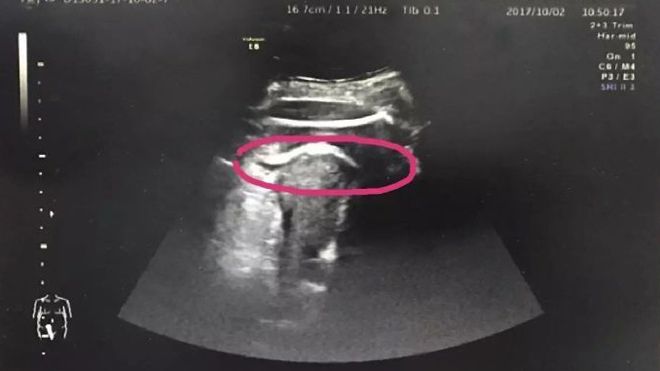

Hy hữu: Mẹ bầu 8 tháng suýt chết vì thai nhi đạp thủng tử cung